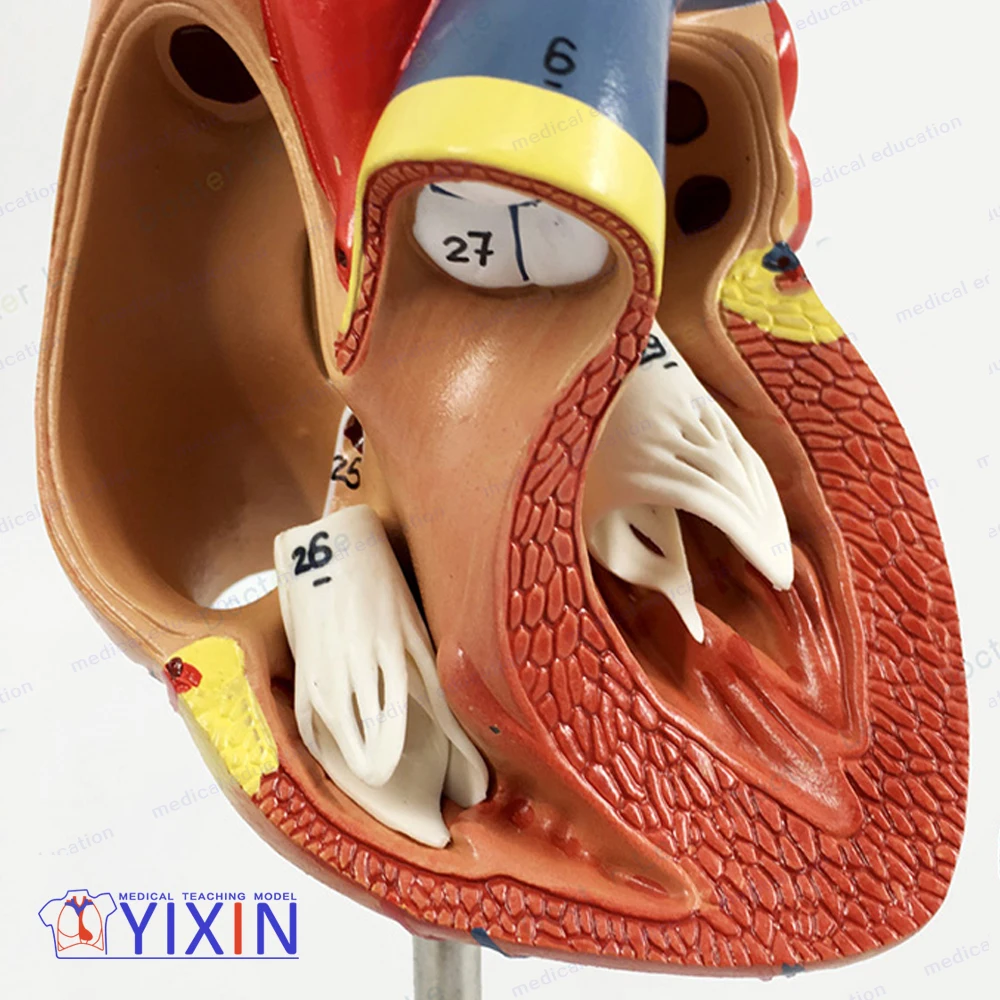

Фотографии и 3D-модели анатомии сердца человека